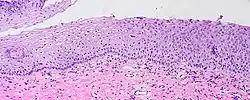

LEEP cone biopsy displaying normal cervical epithelium (far left) progressing to borderline koilocytosis, to LSIL, and to HSIL (far right).

A squamous intraepithelial lesion (SIL) is an abnormal growth of squamous cells on the surface of the cervix; normal squamous cells make up the normal epithelium of the cervix. This lesion can progress to cervical cancer and can be diagnosed using a Pap smear or a colposcopy. It can be treated by using methods that remove the abnormal cells, allowing normal cells to grow in their place.[1] In the Bethesda system, the cytology can be graded as LSIL (low-grade squamous intraepithelial lesion) or HSIL (high-grade squamous intraepithelial lesion).